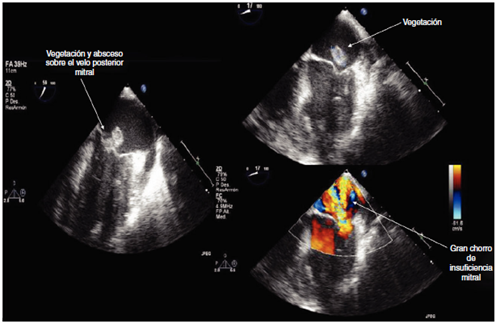

En este episodio de edema agudo de pulmón se contactó con Cardiología realizándose ecocardiograma transtorácico que mostró ventrículo izquierdo con función sistólica global y segmentaria normal, y ventrículo derecho también sin alteraciones. Sin embargo, llamó la atención un chorro de insuficiencia mitral leve, excéntrico, dirigido hacia el septo interauricular, sin poder determinar más sobre la morfología de la válvula mitral por muy mala ventana acústica. Se decidió realizar ecocardiograma transesofágico que mostró absceso de 14 x 8 mm con perforación del velo posterior mitral, que condicionó insuficiencia mitral severa (fig. 3). Se realizó, por tanto, el diagnóstico de síndrome de Austrian (endocarditis + meningitis + neumonía) y se trasladó a cirugía cardiaca en la que requirió recambio valvular mitral con implante de prótesis mecánica sin complicaciones intraoperatorias.

Figura 3 Imágenes de ecocardiografía transesofágica que muestran absceso de 14 x 8 mm con perforación del velo posterior mitral que condiciona insuficiencia mitral severa.